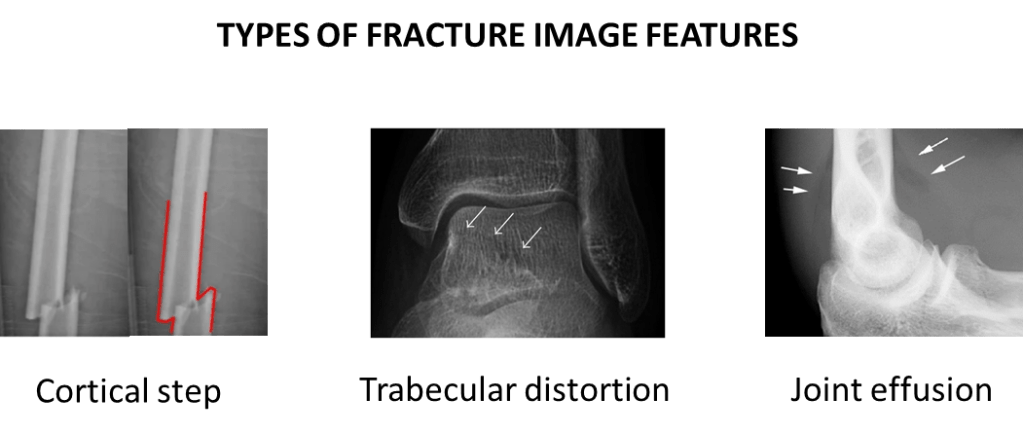

Modern AI systems are often described as “narrow”, meaning they are usually very good at performing a single, often binary, classification task. For example, deciding if a bone is fractured or not. This is fairly simple task, there is a limited set of features that we need to look for, and a fairly consistent type of input image. But even then, we can see that this task is made up of a variety of subtasks and features.

For example, fractures can have different shapes.

Fractures can have different radiographic features.

They can occur in different body parts.

So with all of this variation … is it really a single, narrow task? Can a model even learn to detect fractures, or does it really learn to detect a variety of patterns, involving different combinations of visual features in different sets of images?

We can see that narrowness is not a clearly defined thing, where some models are narrow and some are general. Rather, narrowness is a spectrum. A fracture detector which only looks for displaced skull fractures is far more narrow than a system that is intended to detect any fracture, particularly fractures with visually distinct features such as undisplaced radial head fractures (see the “joint effusion” picture above, the only evidence of the fractured bone isn’t even in the bones, it is a change in the soft tissues).